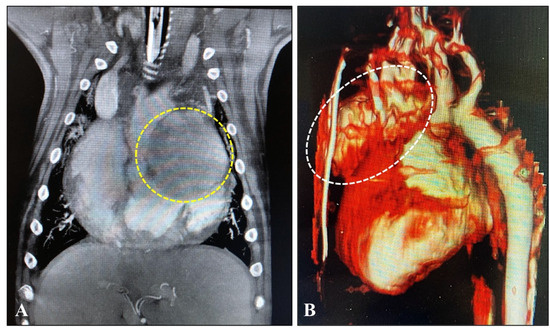

3.4. Diagnostic Imaging and Cytological Findings